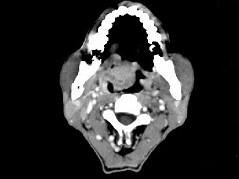

问题 男性,57岁,睡觉打鼾,近来加重,CT扫描如图所示,请选择正确的描述和答案 ( )

选项 A、考虑为鼻咽癌 B、考虑为鼻咽部多形性腺瘤 C、肿块内密度尚均匀,其上方见较多钙化影 D、肿块边缘大部清楚,邻近结构未见明显受侵 E、鼻咽腔偏右侧可见类圆形软组织块影

答案 BCDE